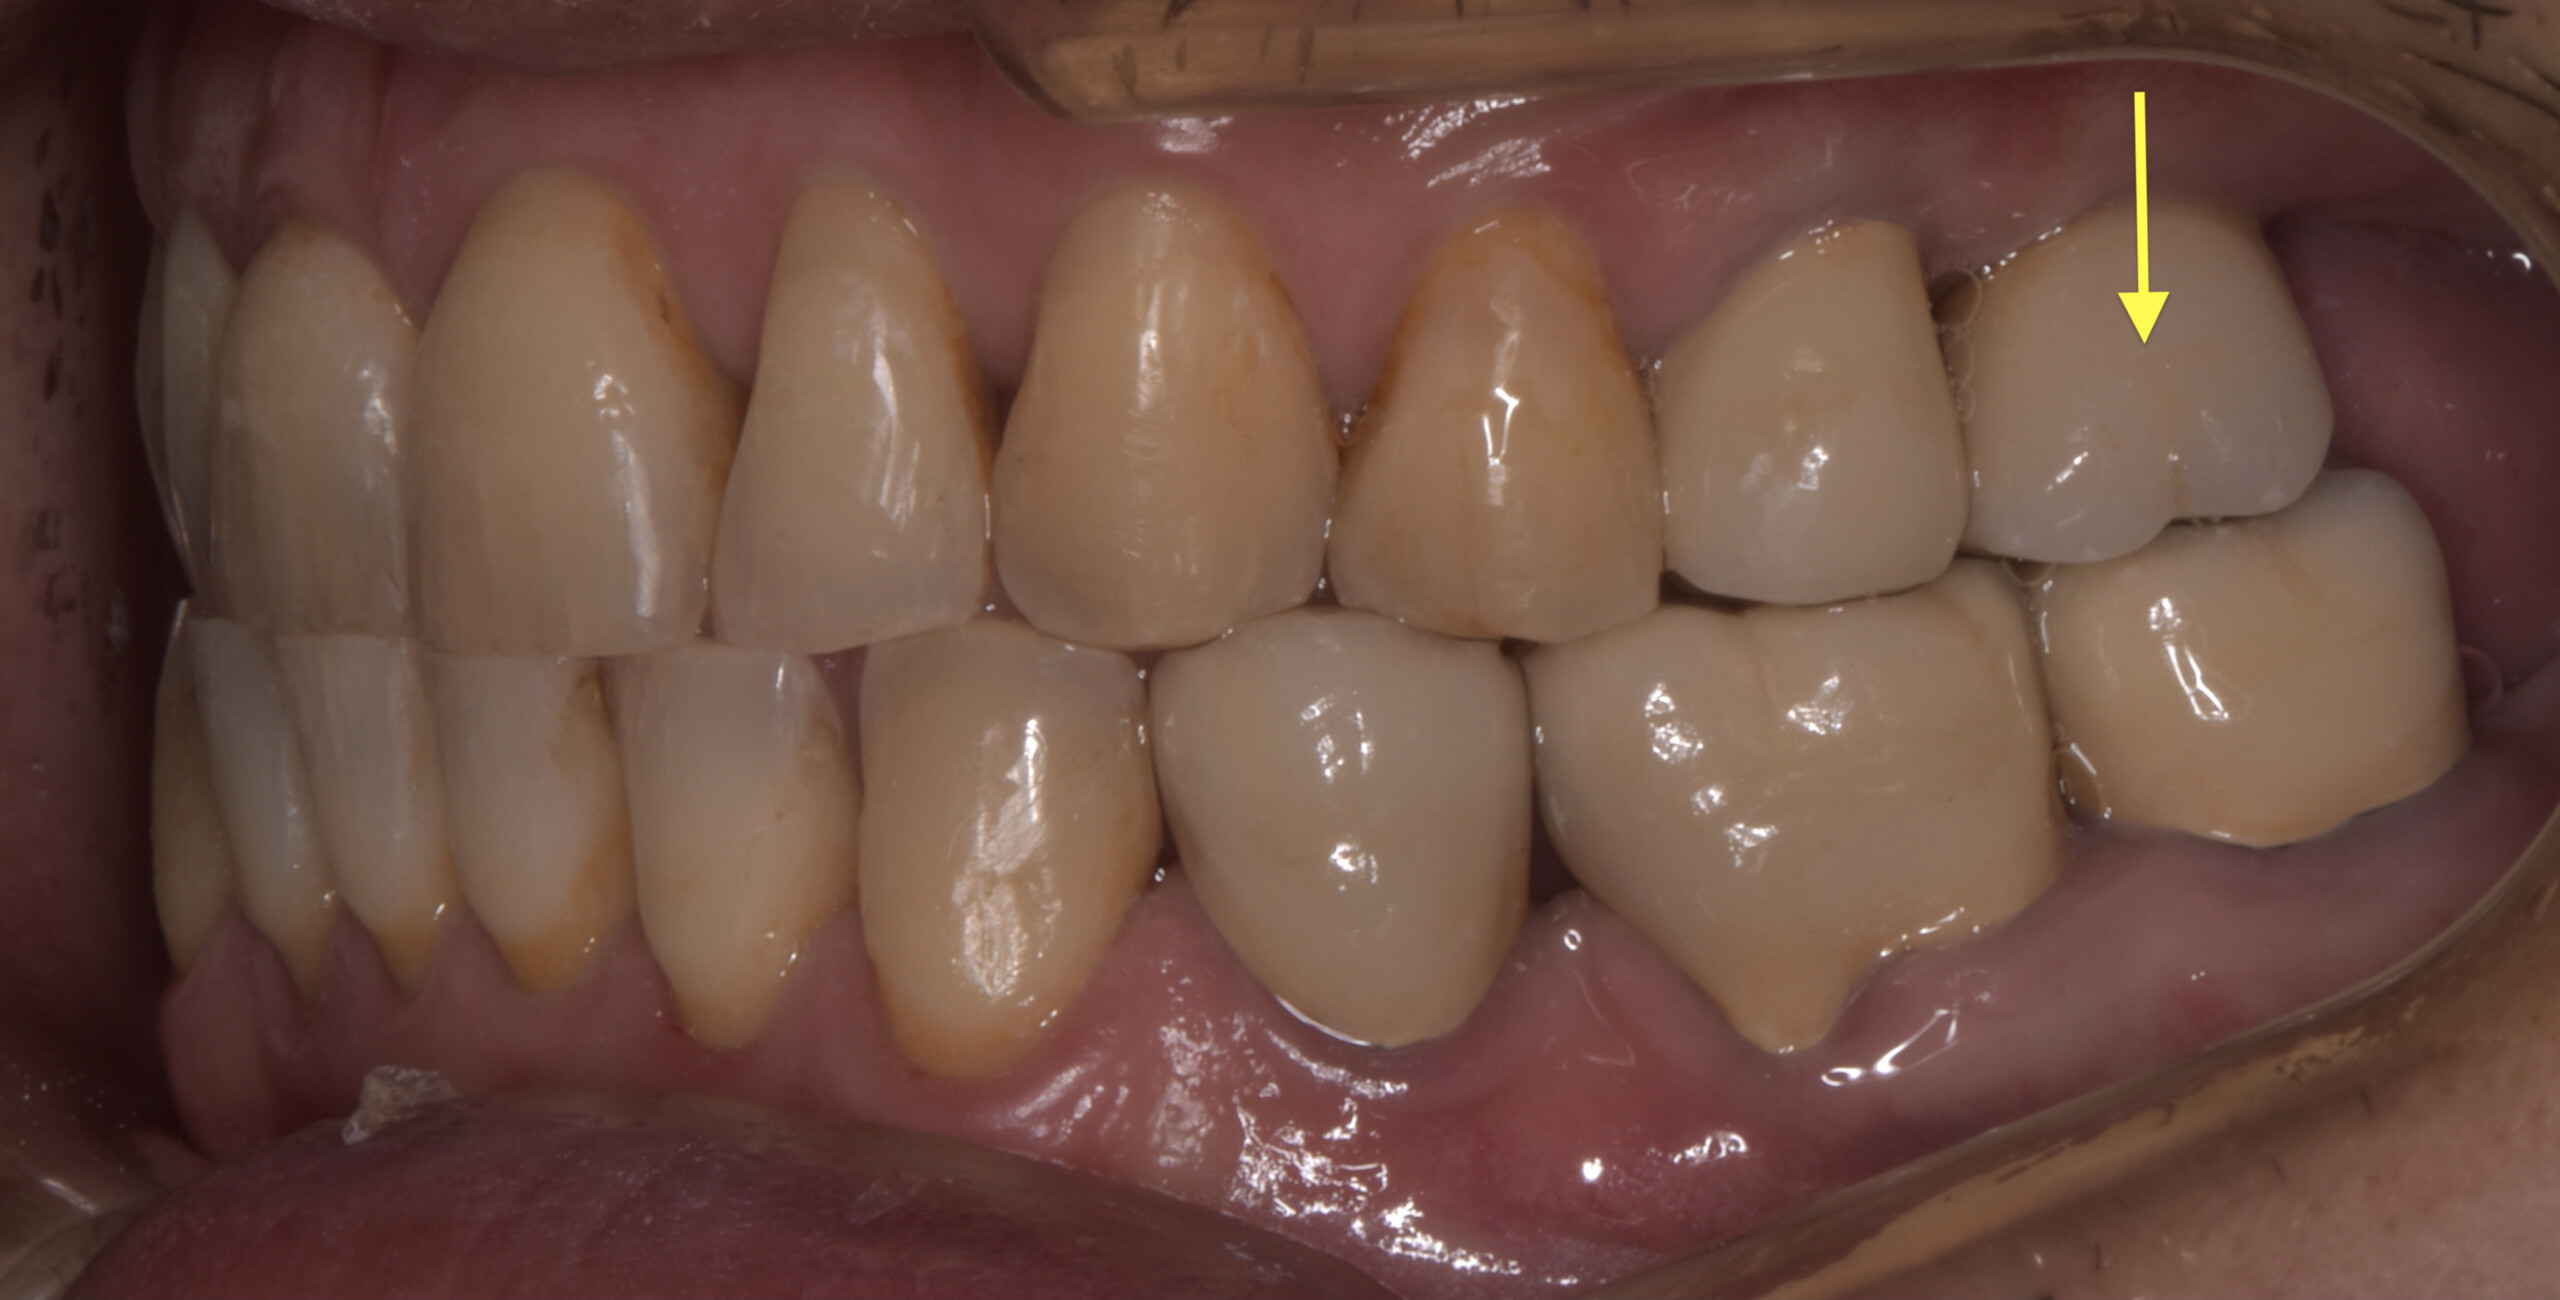

最終のクラウンをセットし咬み合わせのチェックをデジタル機器で行ったところ、患者さんが自覚できない当たりが左奧に見つかりました。黄色の矢印I-26です。

この赤マークが付いているという事はインプラントに負荷が掛かっているという証拠です。